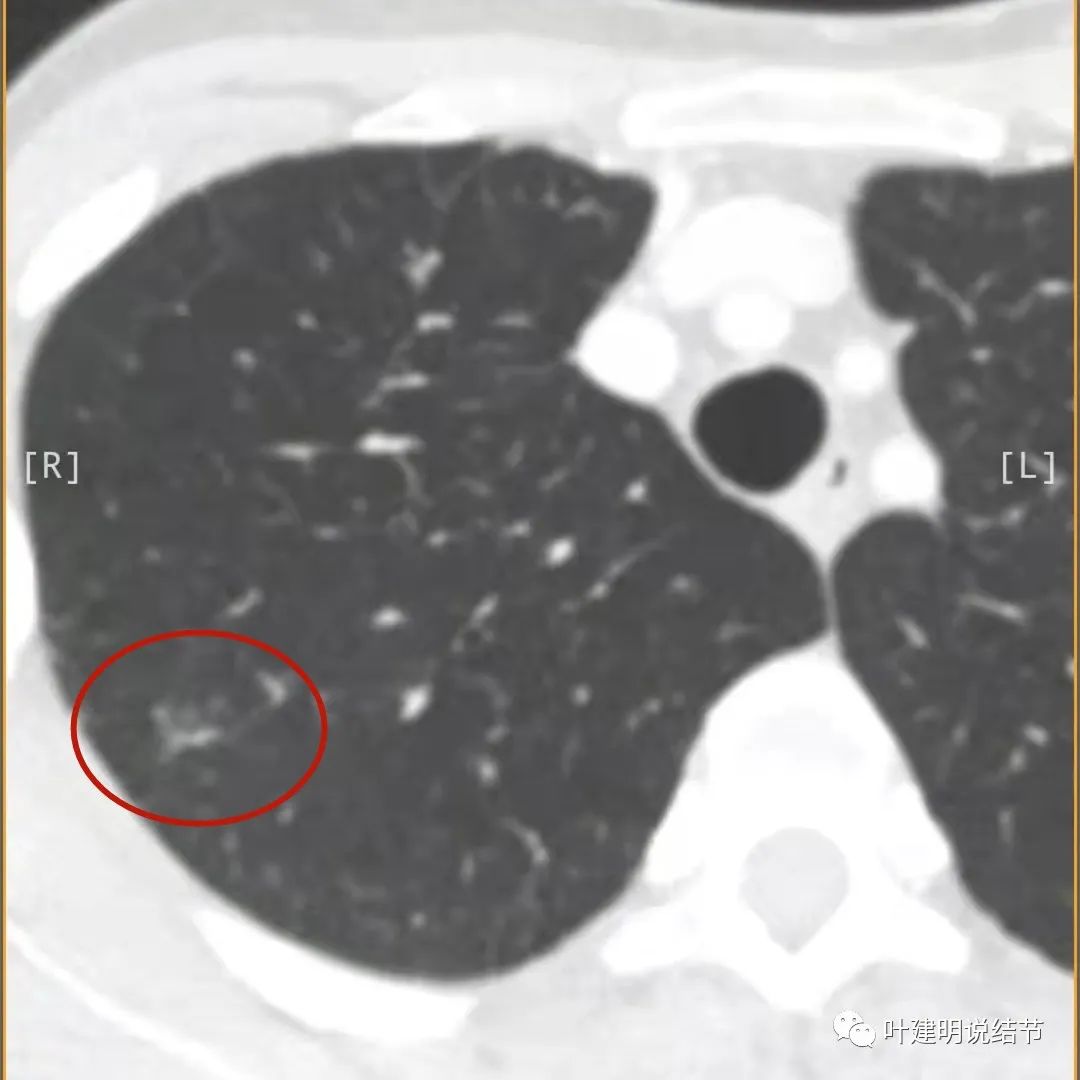

病灶较散,有磨玻璃影,但磨玻璃的边缘模糊不清(砖色箭头),囊壁密度过高(粉色箭头),毛刺样的结构偏长,空洞内壁较光滑,有卫星灶(绿色箭头)

病灶邻近胸膜增厚明显(蓝色箭头);病灶似三角形,边缘平直(桔色箭头);有磨玻璃淡且散,边缘不清(砖色箭头);有卫星病灶(绿色箭头)

有卫星灶,且条索状(绿色箭头),囊壁密度过高(粉色箭头);有空腔征(黄色箭头)